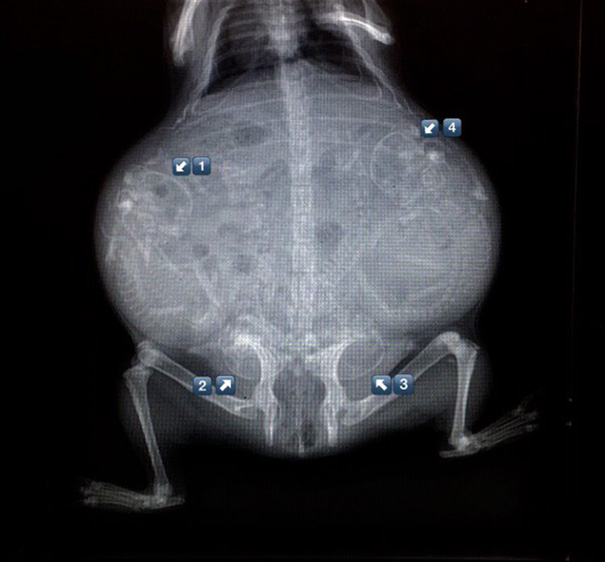

Pregnant Dog X-Ray

These are easier to see then the preg kitten. Looks like a lot of pups in there!

I hope I can't count. There's more puppies then she'll have teats to feed them.

X-rays are done before the due date to check position of babies and count the number of babies. However is it possible to miscount the babies. Babe, my mom's dog, was bred due to the rarity of her coat color. Everybody prepared for 8-10 puppies. Babe delivered 13 puppies.